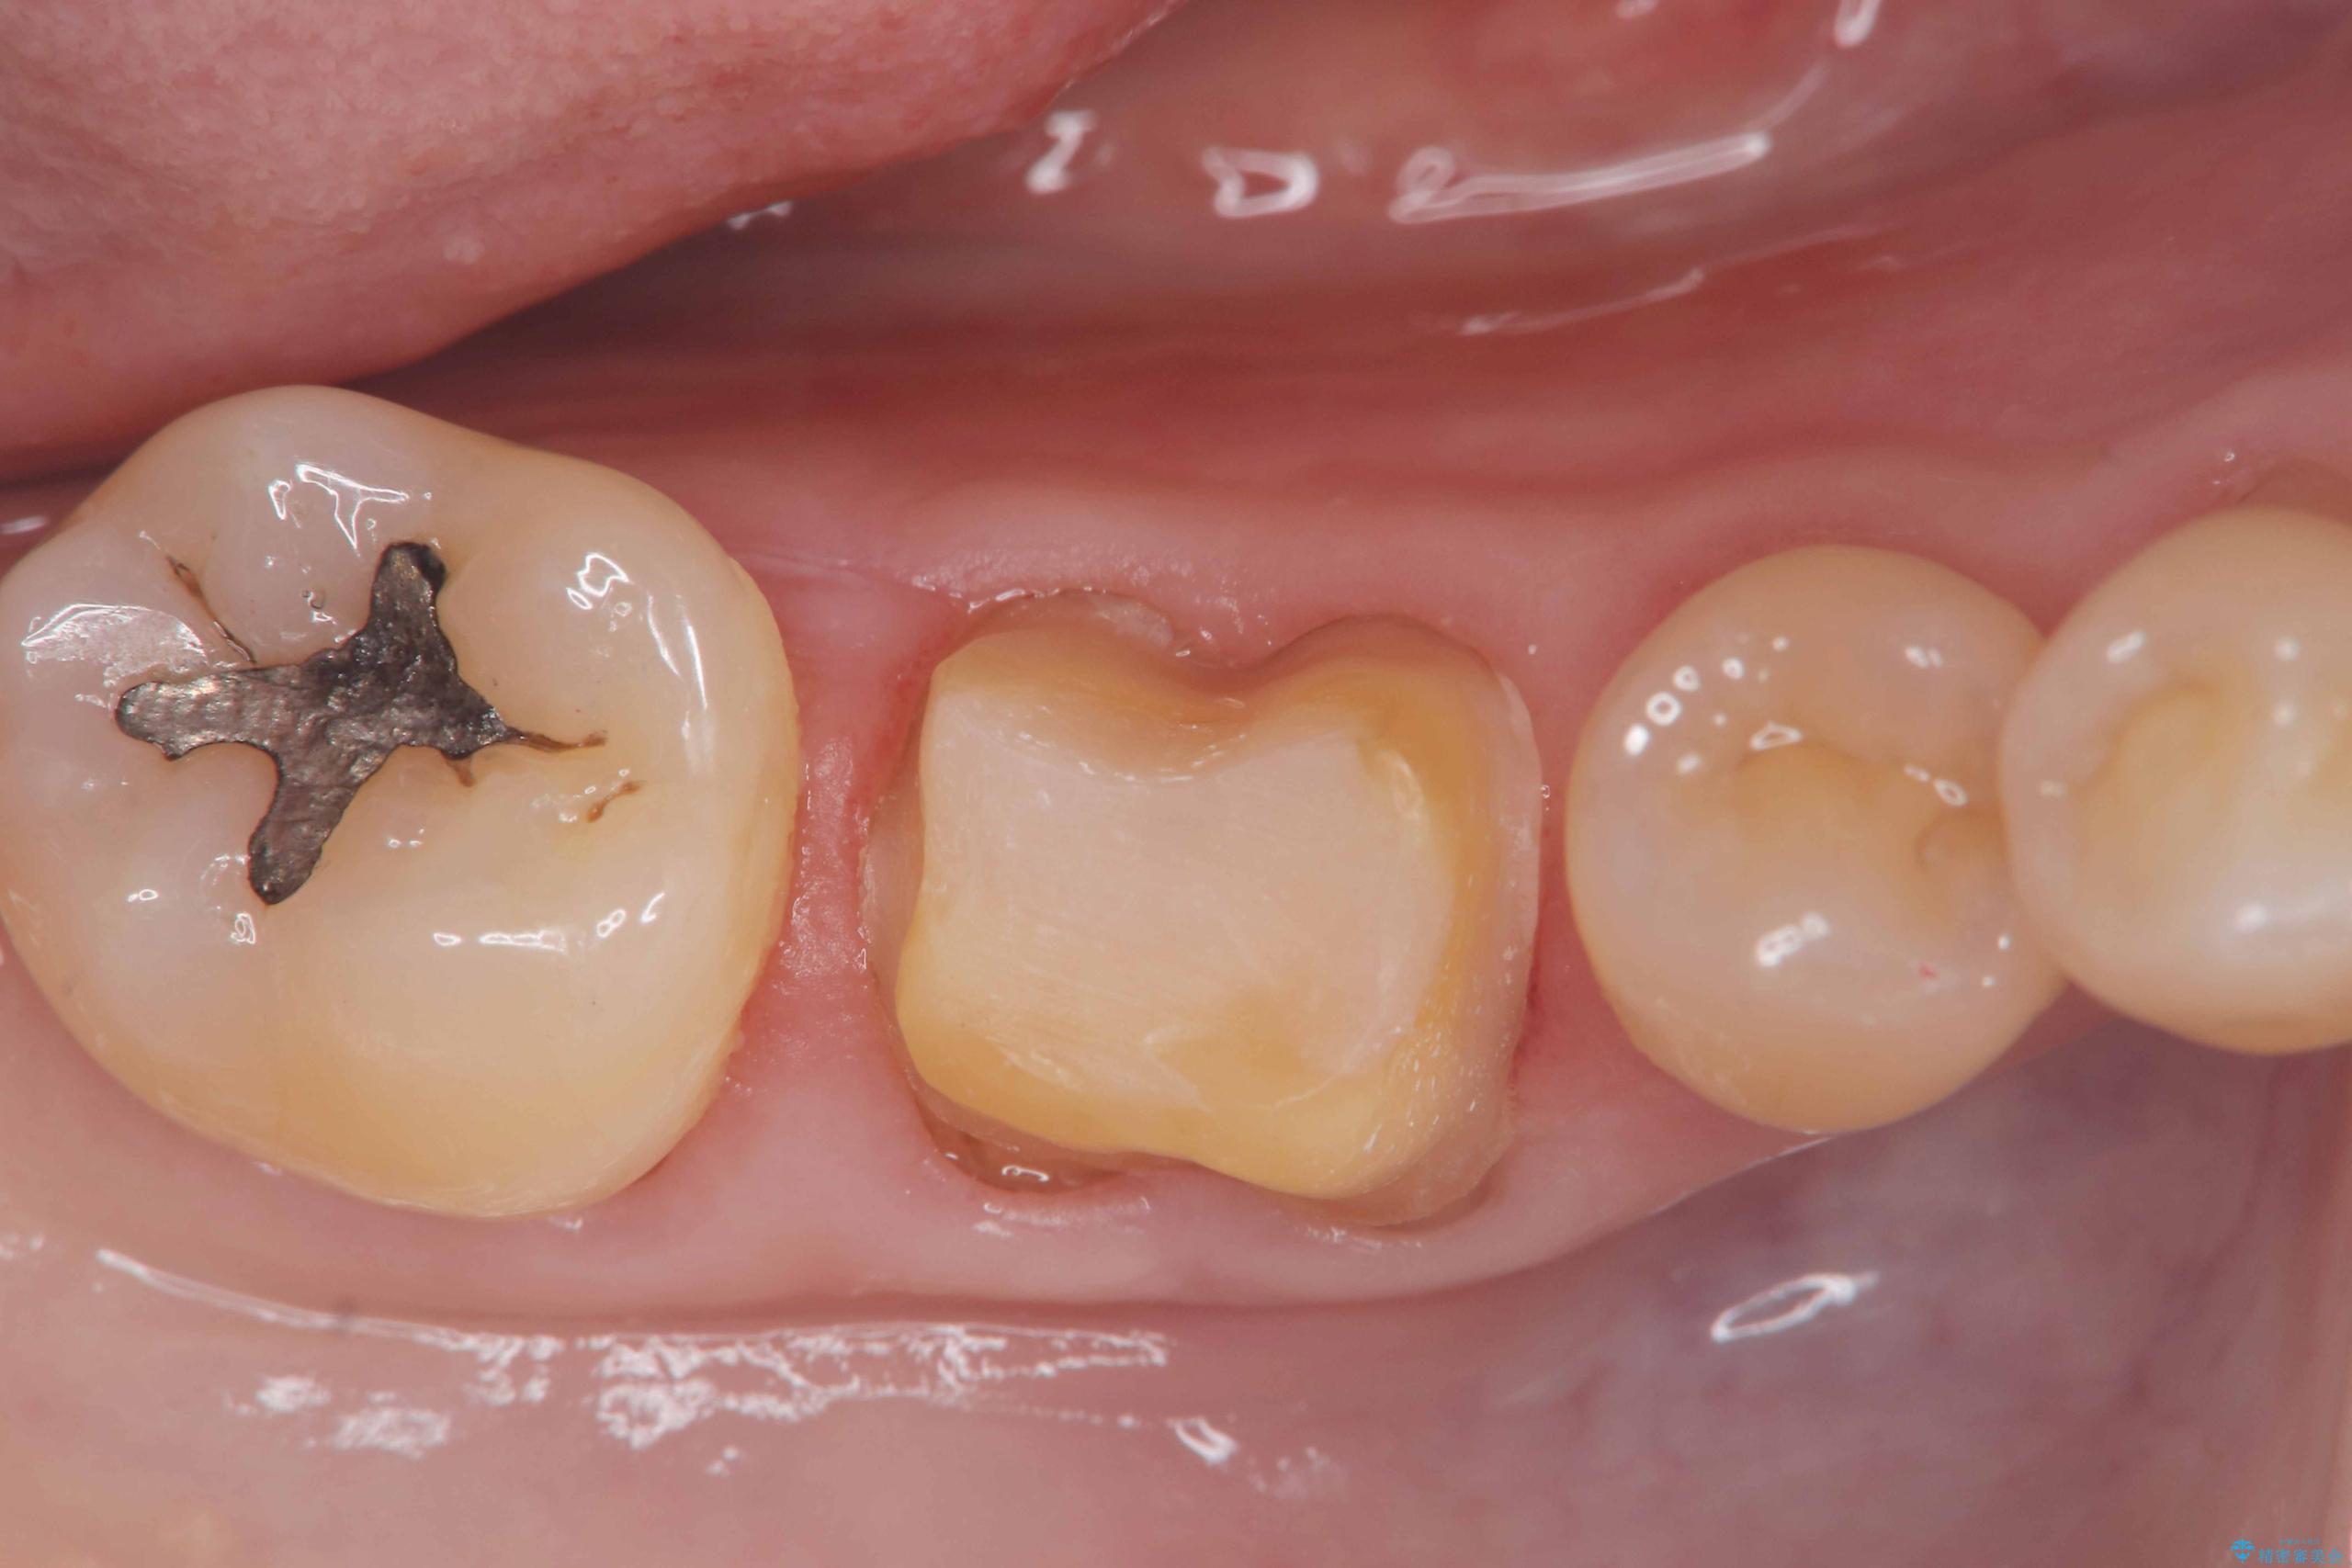

- 「銀歯を白くしたい」を主訴に来院された患者様です。銀歯を外し虫歯を除去後、オールセラミッククラウンで治療を行いました。

銀歯を外して内部の虫歯を丁寧に除去した後、オールセラミッククラウンにて修復を行いました。審美性と機能性の両面で改善が得られ、患者様にもご満足いただきました。